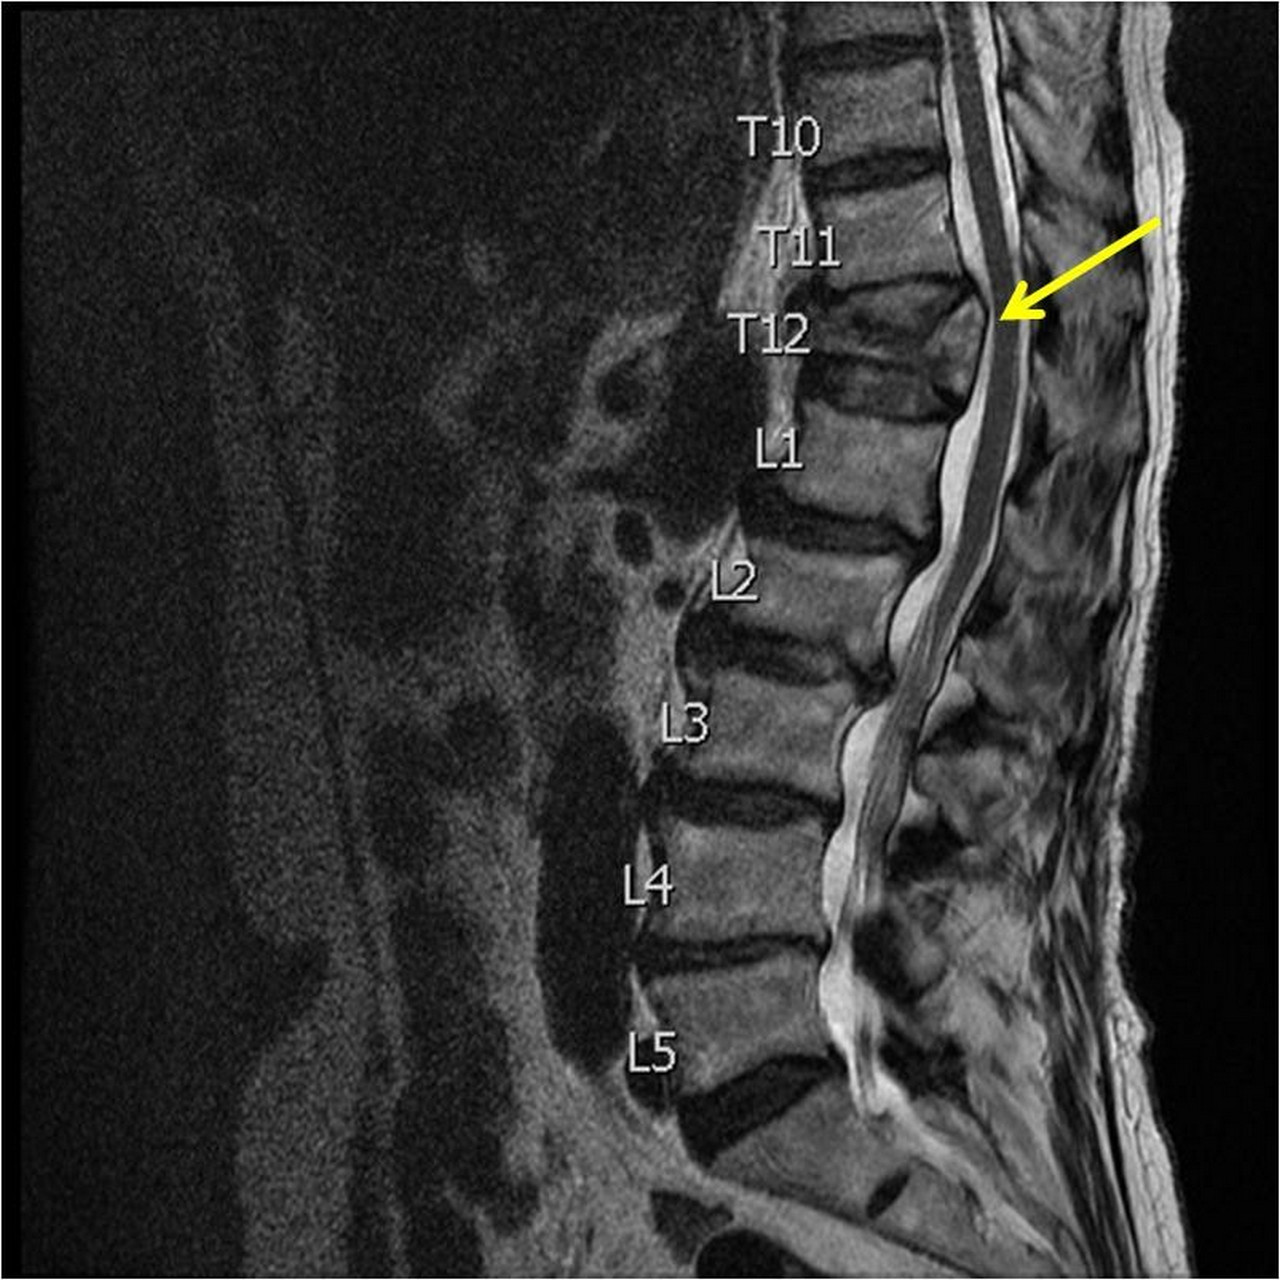

Zona în care coloana este afectată de obicei în cazul unei sărituri cu maşina într-un şanţ